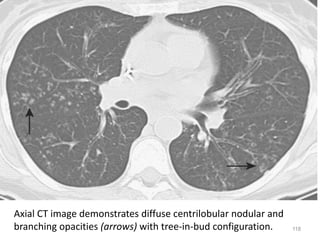

Axial CT image demonstrates diffuse centrilobular nodular and

branching opacities (arrows) with tree-in-bud configuration.